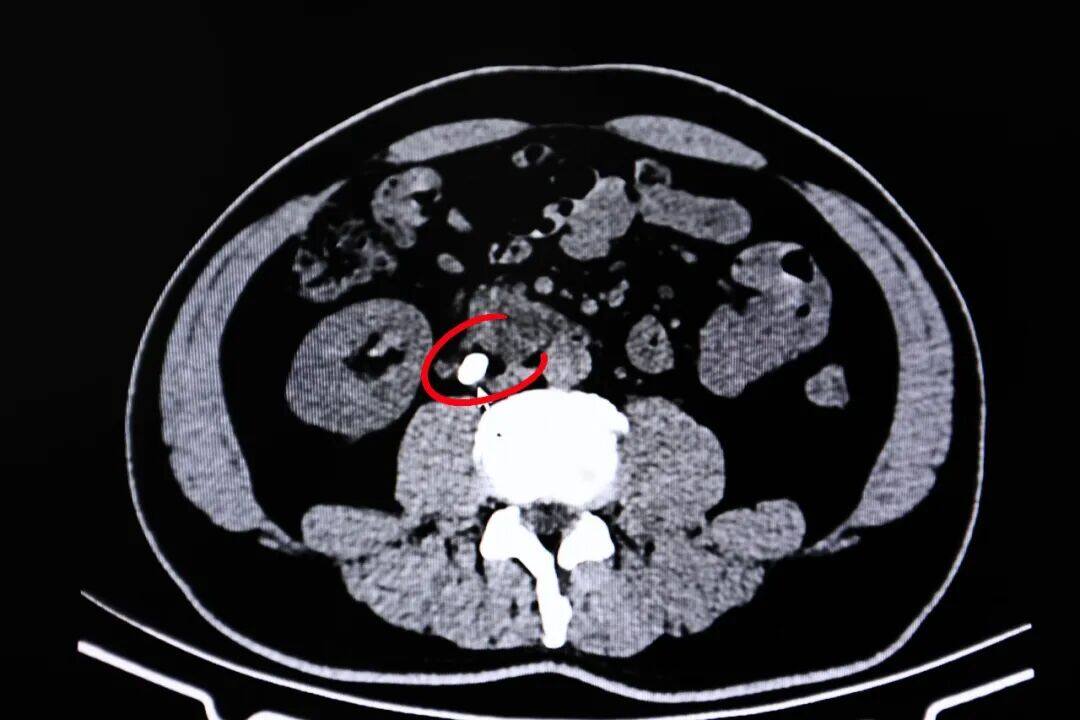

▲患者输尿管结石影像